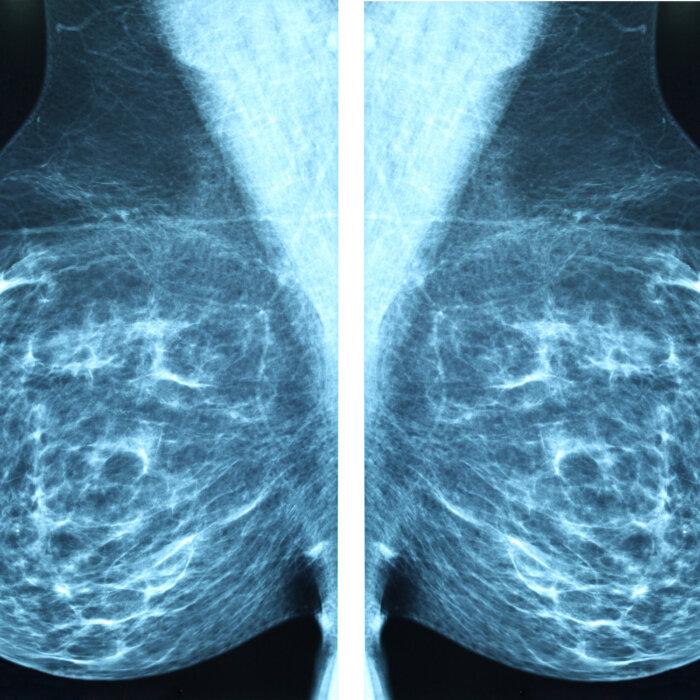

But after returning home, a routine mammogram revealed she had invasive lobular carcinoma—a hard-to-detect cancer that starts in milk-producing glands that turned her life into a whirlwind of information, appointments, and decisions.